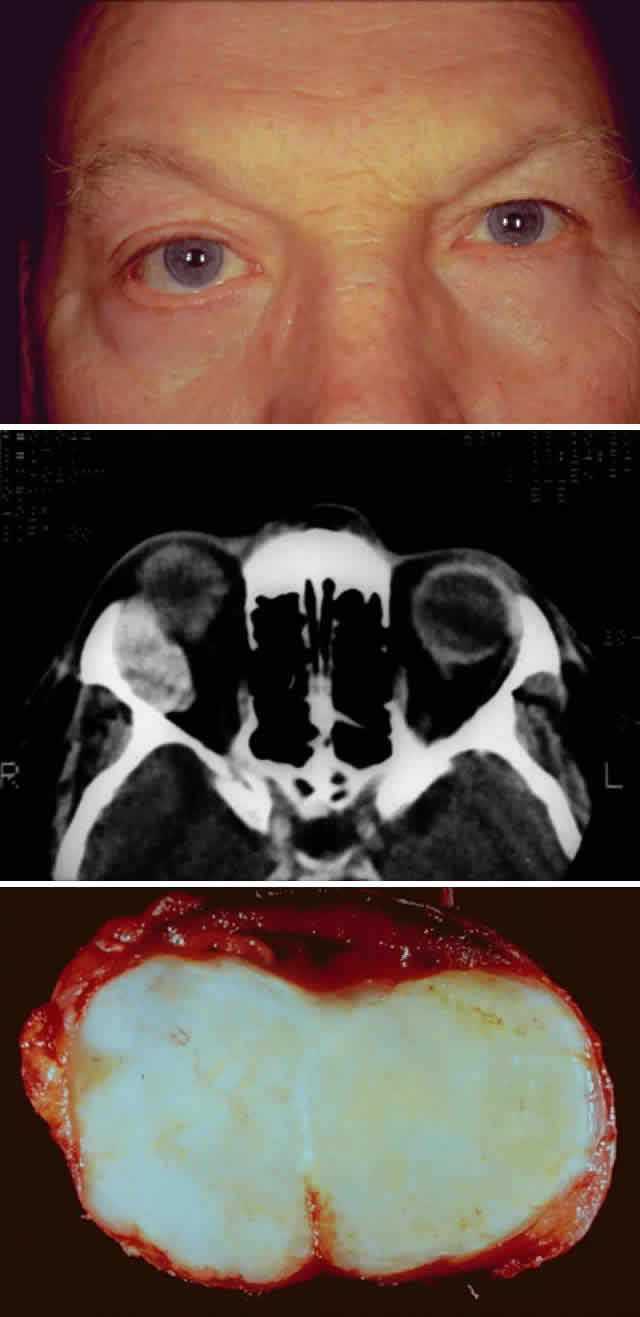

Fig. 2. A 68-year-old woman with malignant lymphoma. A. Clinical photograph demonstrating fullness over the left lacrimal gland fossa, S-shaped contour of the upper eyelid, asymmetric superior sulci, and ptosis. Inflammatory signs are absent. B. Axial computed tomograph demonstrating the classic well-demarcated, oblong appearance of lymphoproliferative diseases of the lacrimal gland. Note that the lesion extends beyond the anterior orbital rim. C. Coronal computed tomograph of the same lesion. Note that the lesion contours to the globe and bone and does not produce any bone changes.

In patients with lymphoproliferative infiltration of the lacrimal gland, a firm, rubbery mass is often palpable in the lacrimal gland fossa. In contrast to inflammatory lesions, lymphoid lesions are usually not tender. Lymphoid lesions contour to the shape of the fossa and surrounding structures, producing a well-demarcated, oblong mass on computed tomography (see Figs. 2B and 2C).9,31 Prominent enhancement after intravenous administration of contrast material is typical for lymphoid lesions.31 The amount of enhancement is similar to enhancement of extraocular muscles. Anterior extension beyond the orbital rim indicates palpebral lobe involvement, which is more typical of lymphomatous lesions and very rare for epithelial tumors of the lacrimal gland.30 In addition, destruction of bone is rare with lymphomatous lesions and therefore is useful in distinguishing lymphomatous lesions from malignant epithelial tumors.9

The incidence of pleomorphic adenomas is equal for both genders, and these neoplasms usually present in the fifth decade of life.15,16 Symptoms may vary depending on the location of the tumor within the lacrimal gland.15,36,37 Pleomorphic adenomas usually involve the orbital lobe and present with symptoms of painless, progressive, nonaxial proptosis and restricted ocular motility (Fig. 4A). These symptoms are typically present for more than 1 year.9,13–15,22 A round or oval mass is present within the lacrimal gland fossa. Smooth erosion (bone modeling) without invasion or destruction of bone is almost always visualized on computed tomography9,15,22 and indicates the slow growth of this disorder (see Fig. 4B).

Fig. 4. A 47-year-old man with a 2-year history of slowly progressive, nonaxial proptosis secondary to a benign pleomorphic adenoma. A. Clinical photograph demonstrating proptosis of the right eye with asymmetric fissures and mild inferior and medial displacement of the globe. B. Computed tomographic image of the pleomorphic adenoma. Note the smooth bone erosion of the lacrimal fossa. The lesion does not extend beyond the orbital rim. C. Photograph of the gross specimen, which has been cut to demonstrate its solid consistency contained within a “pseudocapsule.”